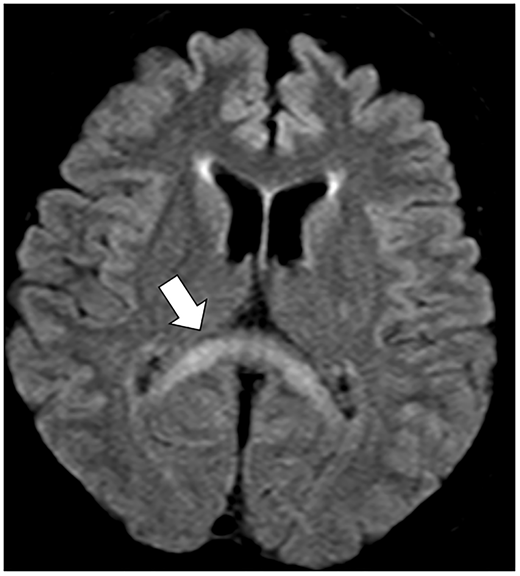

今回は栄養状態が不良、或いは慢性のアルコール多飲者に生じる非常に珍しい脱髄性疾患「Marchiafava-Bignami Disease」のClinical PictureがAcceptされました。タイトルはそのまま「Marchiafava-Bignami Disease」です。

今回のClinical Pictureでは本症におけるMRIのFLAIRやT2強調画像の特徴的な所見である「脳梁膨大部の左右対称な高信号」を取り上げています。

本症は極めて稀であることから、発見から100年以上経過した現在においても症例の蓄積が十分とは言えません。その知名度の低さから明らかな画像所見が存在するにもかかわらずWernicke-Korsakoff症候群と誤診されている症例も多いと考えられます。

慢性的なアルコール多飲者や栄養不良患者の意識障害、多彩な神経症状を認めた場合には本症を鑑別疾患の一つとして、今後挙げていただければ幸いです。